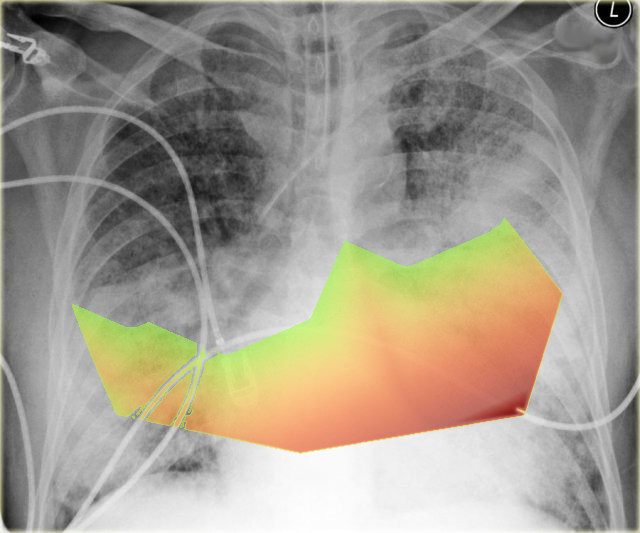

- Diffuse, bilateral airspace opacities involving both image-right (patient-left) and image-left (patient-right) lungs, confluent in the lower zones, consistent with alveolar filling.

- Relative sparing of apices but diffuse ground-glass and consolidation throughout mid-to-lower zones.

- No large pleural effusion or pneumothorax detected; costophrenic angles partially obscured by consolidation.

- Cardiothoracic ratio appears at the upper limit of normal but difficult to fully assess due to diffuse opacities.

The most likely diagnosis is acute respiratory distress syndrome (ARDS) or severe pulmonary edema. The diffuse bilateral alveolar infiltrates without clear focal consolidation pattern, presence of endotracheal intubation, and indistinct vascular margins raise suspicion. Cardiomegaly is not prominent, which argues slightly against isolated cardiogenic pulmonary edema, making ARDS from sepsis, aspiration, or severe infection more likely.